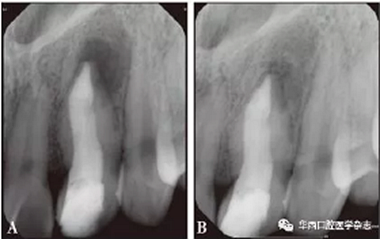

A:術(shù)后3個月;B:術(shù)后1年。

圖 4 術(shù)后根尖片

根尖屏障術(shù)后1年(2018年3月21日)復(fù)診攝X線片,患牙根尖區(qū)低密度透射影像明顯縮小,根尖區(qū)趨于愈合(圖4B)。

因患者出國未歸,根尖屏障術(shù)后3個月(2017年7月24日)回國復(fù)診自述無不適,叩診陰性,冠方充填物完整無脫落,X線片示根尖區(qū)低密度透射影像有縮小跡象(圖3A)??紤]患牙管腔過大,管壁過薄,容易發(fā)生牙折,與修復(fù)科醫(yī)生會診,擬行纖維樁加固術(shù),橡皮障隔離術(shù)區(qū),去除原充填物后顯微鏡下可見iRoot BP Plus固化完全,上端熱牙膠充填3 mm,2根25號纖維樁體置入根管粘接固位(圖3B),冠部樹脂修復(fù)(圖3C、3D),攝X線片(圖4A)。